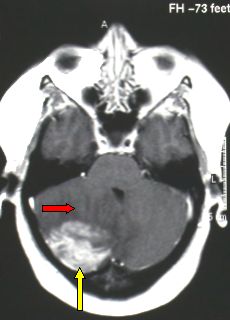

adriapel Inviato 28 Gennaio, 2011 Autore #5 Inviato 28 Gennaio, 2011 Ho letto il libro del quale tu accenni. E' veramente un bel testo. Mi sono però basato su affermazioni di Plutarco ed altri storici che definiscono Cesare in ottima salute e precisamente ci informano che le crisi epilettiche e i mal di testa (cefalee) comparvero la prima volta nel 45 a C quindi un anno prima di morire per mano dei congiurati. Ebbene io credo che Cesare possa aver avuto una lesione cerebrale da tumore primitivo o metastatico che giustificava l'inizio improvviso di questi sintomi e qundi anche lo stato cachettico (dimagramento repentino). Non ho letto il libro di Macchi e non sò quale ipotesi vengano formulate. Riporto una immagine TAC cerebrale che mostra un tumore dell'encefalo. Essendo il cervello racchiuso in una scatola rigida rappresentata dal cranio, qualsiasi lesioni cerebrale è in grado di aumentare la pressione all'interno del cranio e i sintomi che ne derivano sono quelli descritti da Plutarco. Ottaviano nascose debitamente le carte che parlavano dello stato di salute di Cesare Un caro saluto Adriapel. 1 Cita